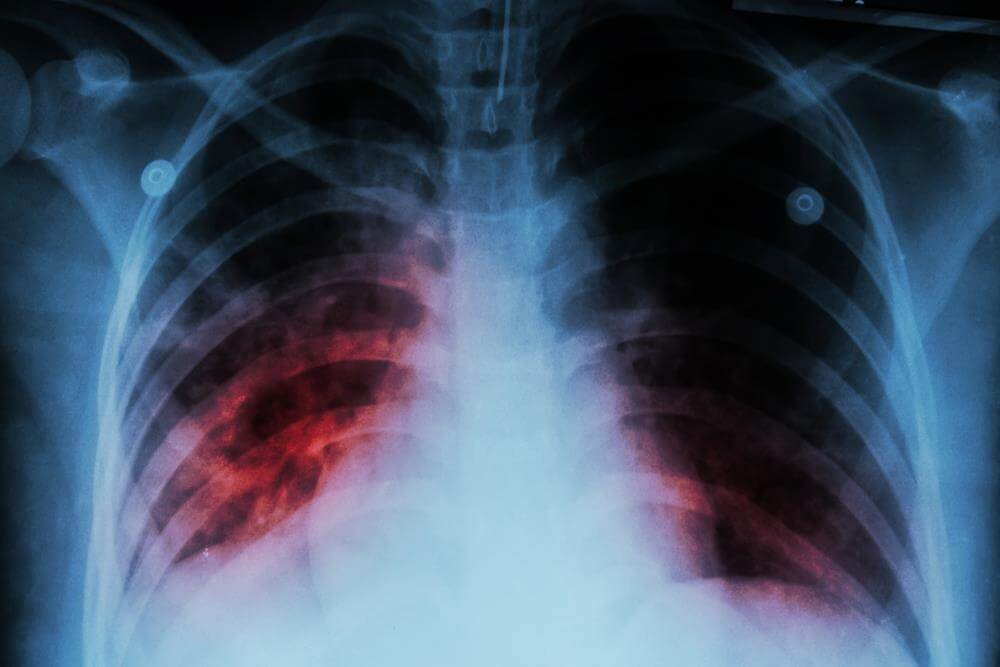

最后,小女孩经过肺部检查,确诊为肺部含铁血黄色沉着症,如果发现的再晚一点,孩子很有可能因为肺部纤维化导致呼吸困难甚至有死亡的危险。最终,小女孩经过系统的治疗贫血的情况慢慢得到了改善。

但是需要注意的一点是,对于儿童来说,如果感冒或者流感没有得到及时治疗,很容易进展为肺炎。不同的肺炎表现出的痰液颜色也是不一样的。

根据临床经验,如果痰液是铁锈色的,肺炎主要是由肺炎链球菌引起的;金黄色葡萄球菌则引起黄浓痰;肺炎克雷伯杆菌引起果冻样暗红色痰;绿色浓痰则大多是由铜绿假单胞菌引起的。